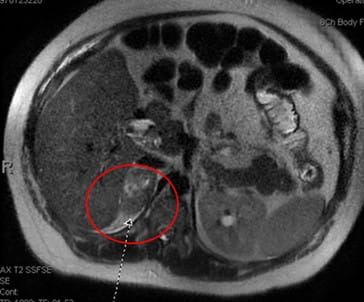

A 28-year-old female with a history of irritable bowel syndrome (IBS) and asthma presented to a UPMC emergency room with nausea, vomiting, and right sided abdominal pain during the 35th week of her first pregnancy. An abdominal MRI revealed a 4.7 x 2.8 cm right adrenal hemorrhage (see Image 1).

Image 1: MRI without contrast remarkable for a 4.7 x 2.8 cm indeterminate right adrenal lesion with associated perinephric fluid. This finding is concerning for adrenal hemorrhage.